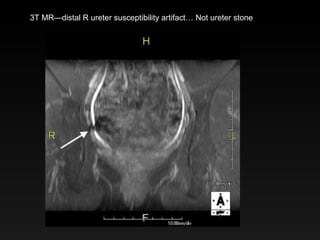

3T MR—distal R ureter susceptibility artifact… Not ureter stone

3T MR—distal Rureter susceptibility artifact… Not ureter stone